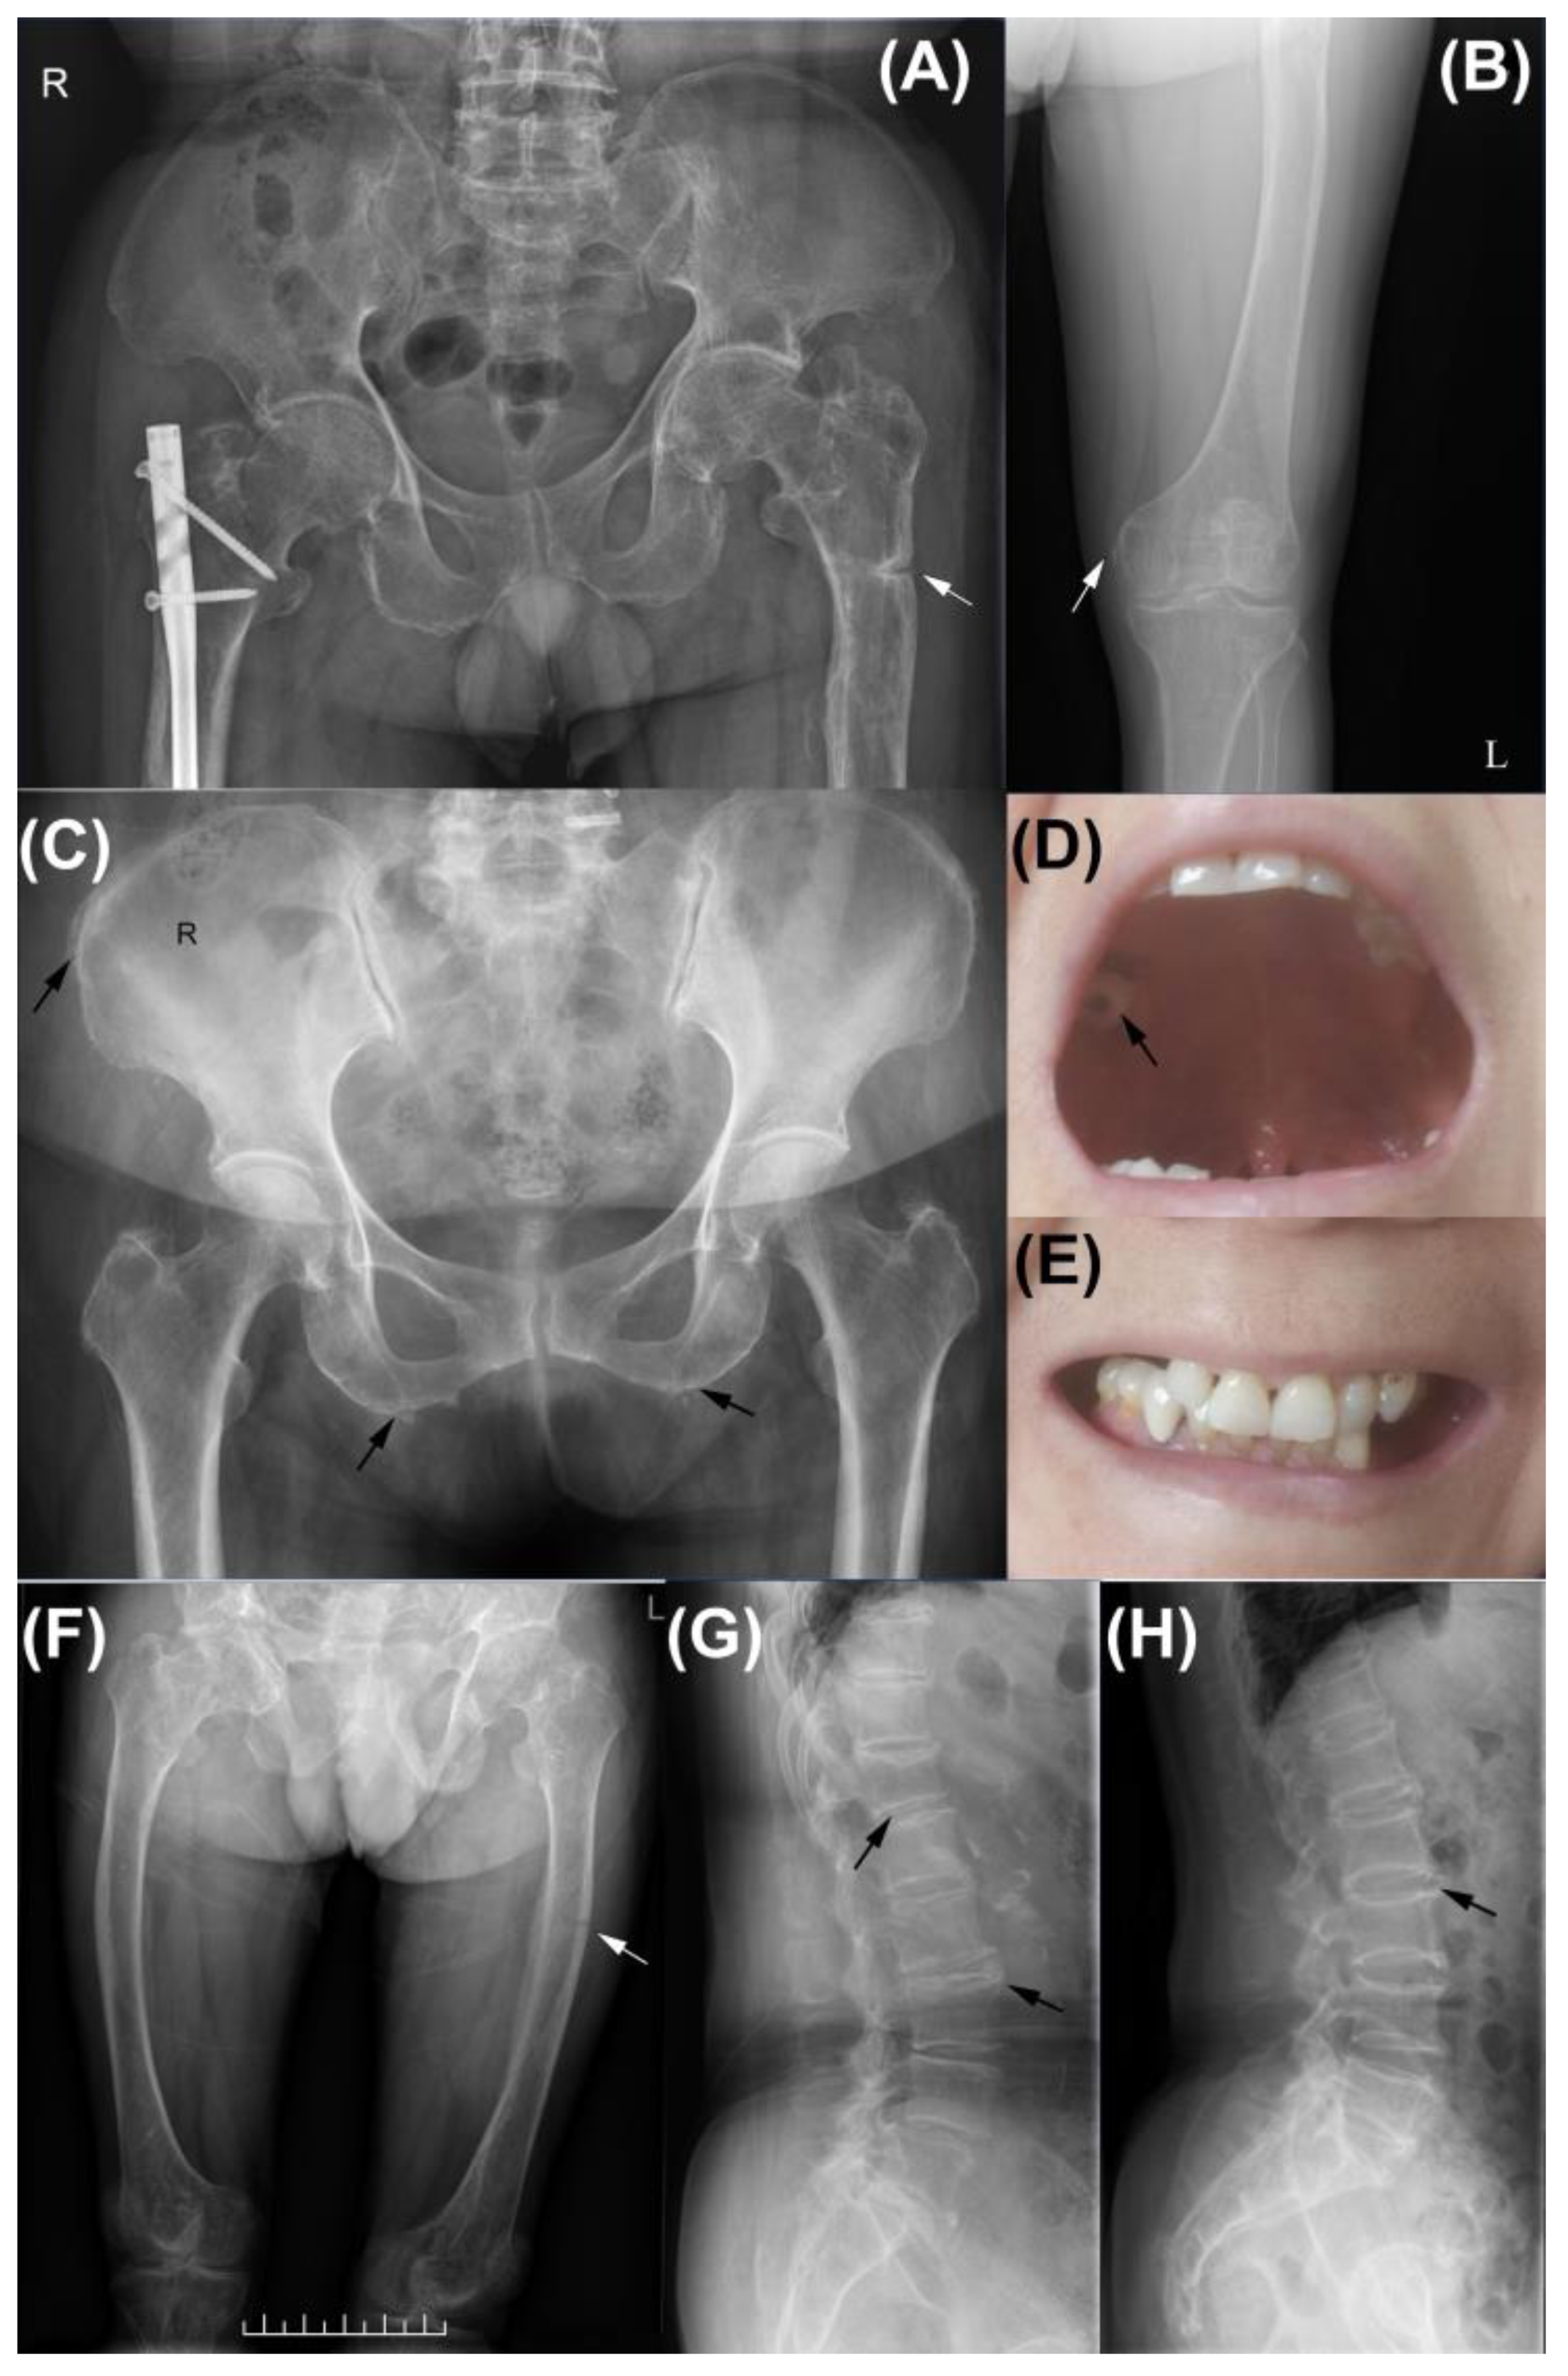

| FAM1-3 | male | 38 | early loss of deciduous teeth, abnormal teeth eruption | RF, mVF, pseudofracture | leg pain | growth retardation, bowing legs | - |

| FAM2-4 | female | 70 | early loss of permanent teeth, dental caries | mVF | backache | - | |

| PT-3 | female | 62 | dental caries, early loss of permanent teeth | AF | arthralgia | fatigue | RA * |

| PT-13 | female | 54 | early loss of permanent teeth | FF, pseudofracture | leg pain | CPPD, short stature | - |